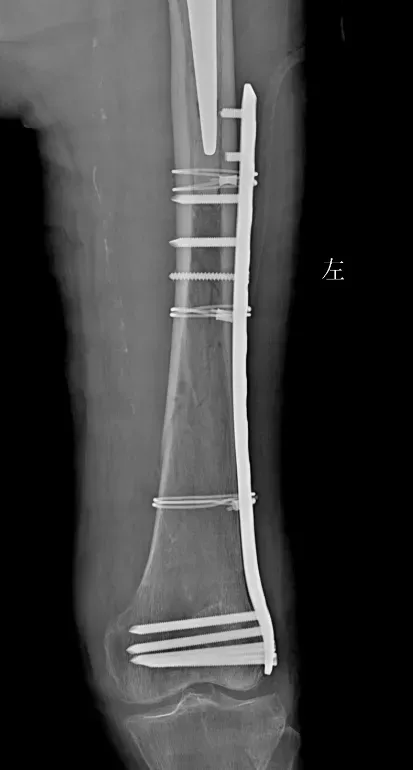

案例二

91歲的患者因“捧傷致左髖部疼痛伴活動受限4小時”入院。入院診斷為左股骨粗隆間骨折,伴有貧血、肺氣腫、帕金森病、阿爾茲海默病、泛發(fā)性帶狀皰疹、陳舊性腦梗死、胸8椎體陳舊性壓縮性骨折等多系統(tǒng)疾病。入院后,患者接受了全面的輔助檢查,并給予患肢抬高制動、止痛、補液、皮牽引等對癥治療。多學(xué)科團隊(MDT)進行了綜合評估和術(shù)前討論,決定在腰硬聯(lián)合麻醉下行左股骨粗隆間骨折閉合復(fù)位Intertan內(nèi)固定術(shù)。

術(shù)前

術(shù)后

術(shù)后,患者轉(zhuǎn)入重癥監(jiān)護室觀察2天,病情穩(wěn)定后轉(zhuǎn)入普通病房。在醫(yī)護人員的精心照料下,患者恢復(fù)良好,左髖部疼痛明顯減輕,活動能力逐步恢復(fù)。